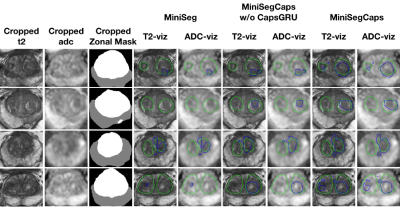

Fig.3 illustrates a visual comparison of the cropped T2, cropped ADC, cropped zonal mask, lesion ground truth, and predicted lesion mask by MiniSegCaps on T2 and ADC images. Our model successfully produced satisfactory segmentation of prostate cancer and revealed the spatial relationship between the zonal mask, lesion on T2, and ADC, which might help lesion location and classification. We also obtained consistent segmentations across adjacent slices within one volume, as shown in Fig.4. Our MiniSegCaps obtained better results than MiniSegCaps w/o CapsGRU, which indicates that CapsGRU captured the spatial information across adjacent slices as expected, boosting the prostate cancer segmentation performance. Moreover, our model achieved acceptable performance on BPH segmentation as shown in Fig.6.

Fig. 3. Visualization of lesion segmentation results among different cases. The yellow contour is the ground truth, and the red contours are from the deep learning predictions.

Fig. 4. Visualization of lesion segmentation results on eight slices from one case. The yellow contour is ground truth, and the red contours are predictions from the MiniSegCaps without or with CapsGRU. MiniSegCaps with CapsGRU can better delineate the prostate cancer contours across different slices in one case compared to that without CapsGRU.